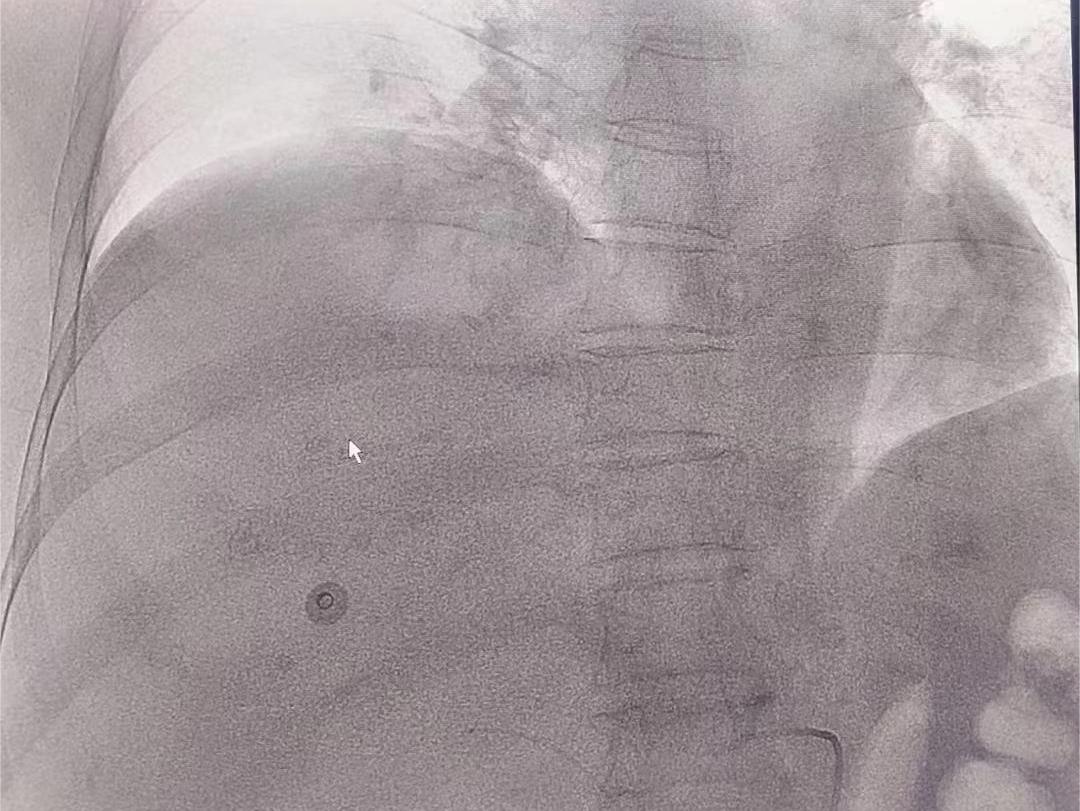

随着全国各地疫情陆续放开,不少城市再一次按下了暂停键,往日车水马龙的街道,人声鼎沸的商场,此刻空无一人。病毒无情,人有情。通用环球西安西航医院呼吸肿瘤老年病科,收治了一位老年72岁肝右叶巨块型肝细胞癌伴门静脉、下腔静脉、肠系膜上静脉癌栓患者的患者,秉持着生命至上的原则,业务主任成佳带领团队认真分析病情,为患者制定了HAIC手术方案,后泵入FOLFOX4方案化疗,此术式为我院首次开展,为患者治疗争取了宝贵时间。

HAIC治疗(Hepatic Artery Infusion Chemotherapy )即肝动脉灌注化疗,是在DSA引导下经股动脉插管至肝动脉并保留导管将化疗药物长时间持续注入肿瘤供血动脉的一种区域性局部化疗,是介入治疗的一种方式。HAlC治疗已被写入国家卫健委《原发性肝癌诊疗指南(2022版)中。